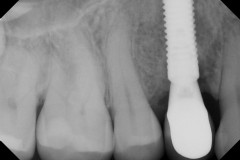

This mouth had recession on just one tooth with very little bone to support the tooth. The area needed support and thickness. The tissue was placed and the area now has thicker tissue to withstand the forces that the patient needs to place on it.

Click on a thumbnail to view the before and after photos.